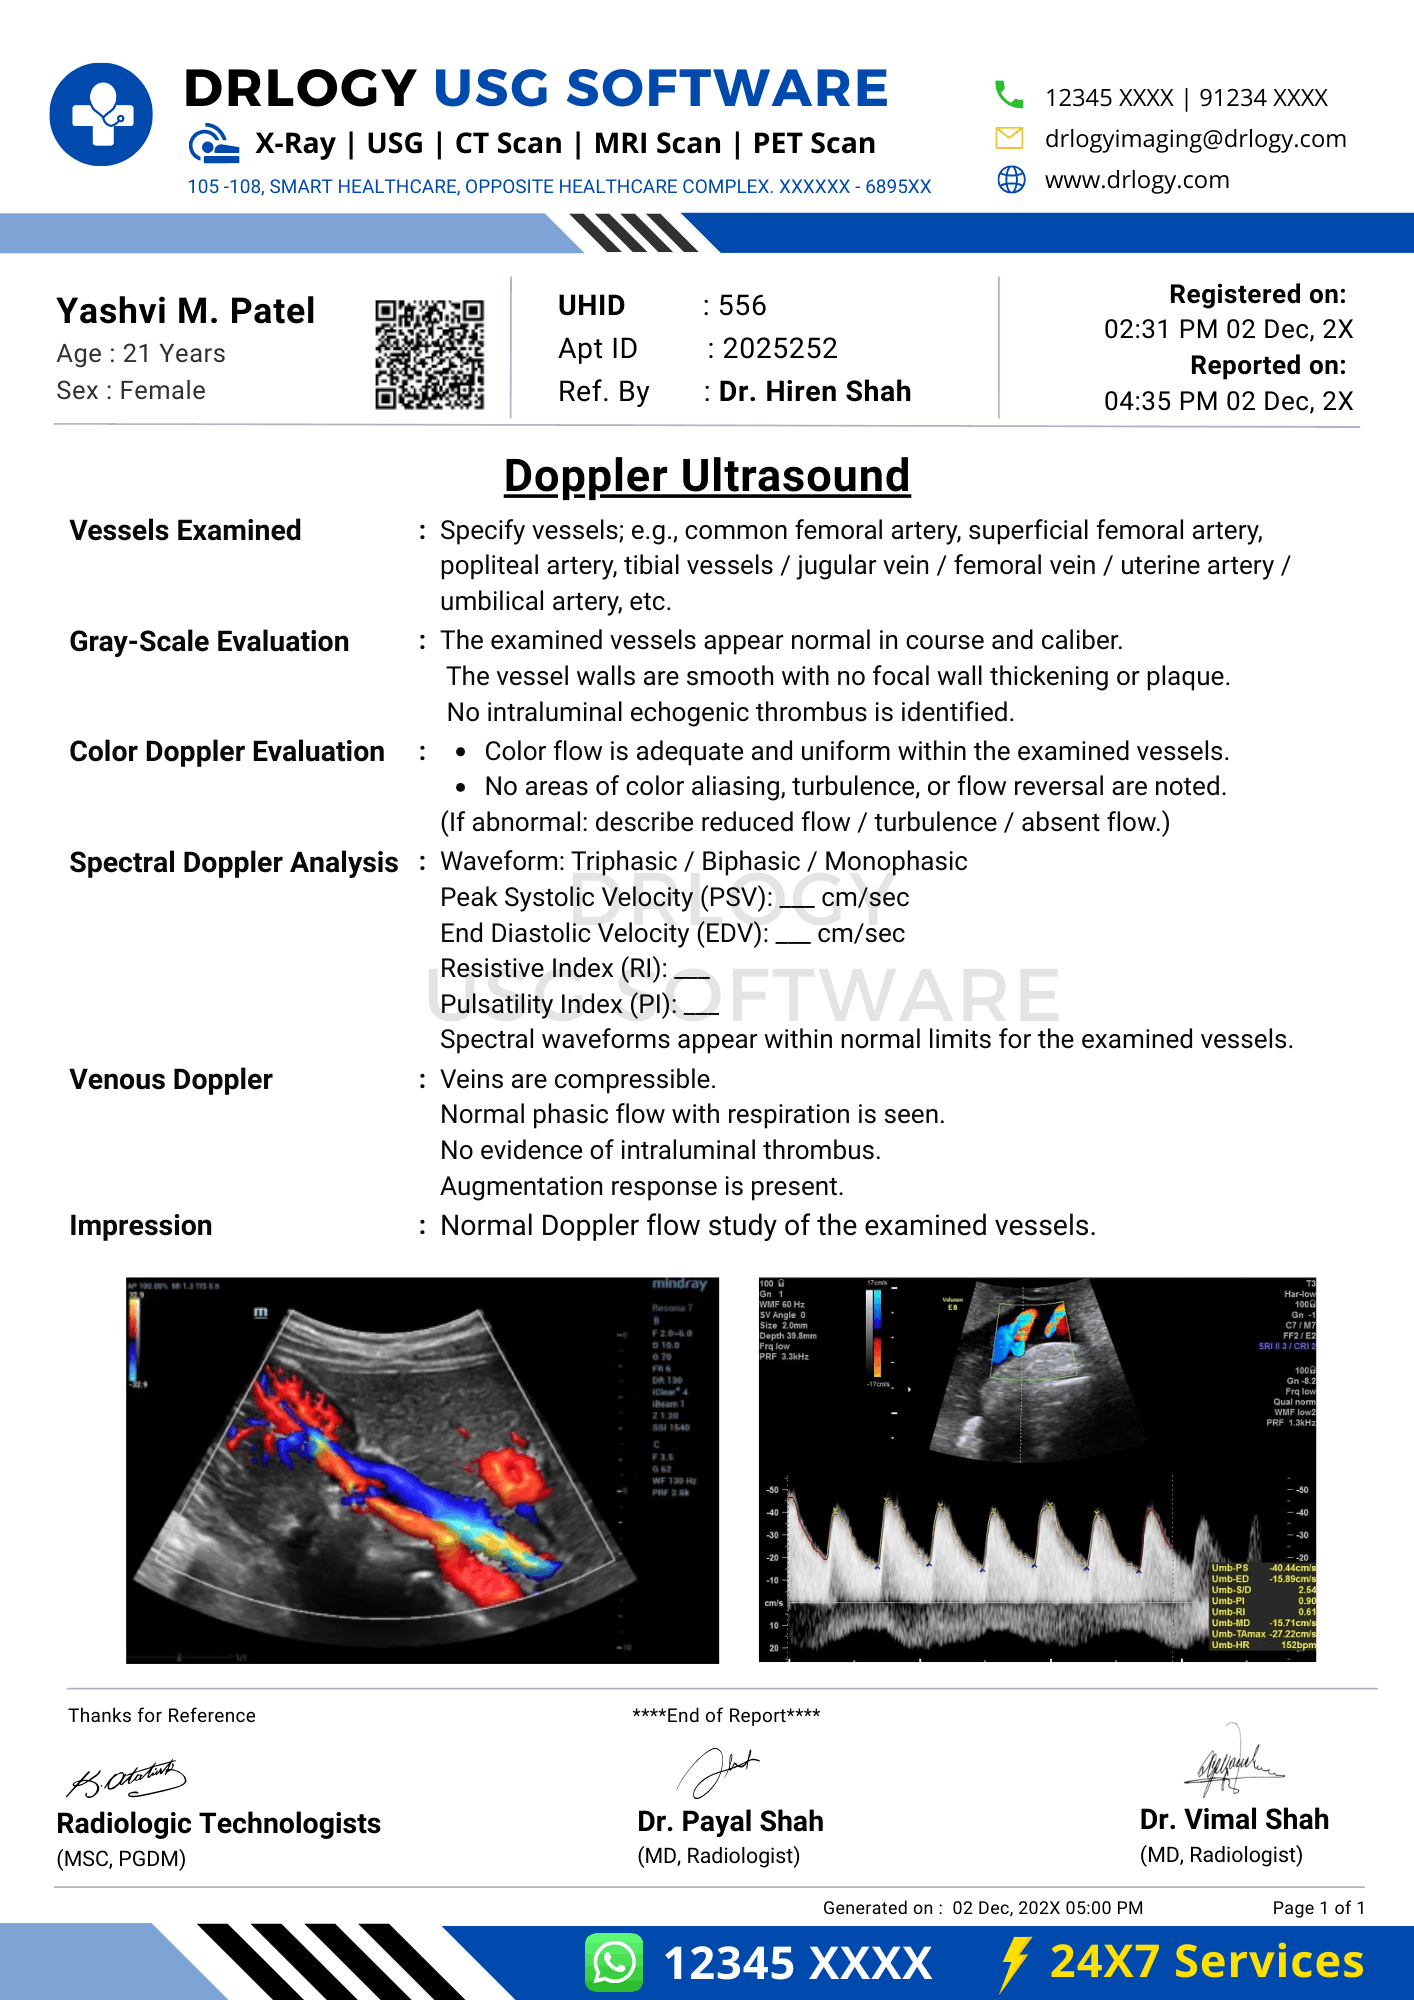

Normal Doppler Ultrasound Report Format (Sample)

- Patient & Study Information:

- Patient: [Name], [Age]

- Study Date: [DD-MM-YYYY]

Examination: Doppler Ultrasound

Clinical History / Indication:

Vascular evaluation.

Technique / Protocol:

Color and spectral Doppler evaluation performed.

Findings:

The examined vessels show normal patency with laminar flow. Spectral waveforms and velocity parameters are within expected limits.

Impression / Conclusion:

No significant Doppler abnormality detected.

Limitations:

No significant technical limitation noted.